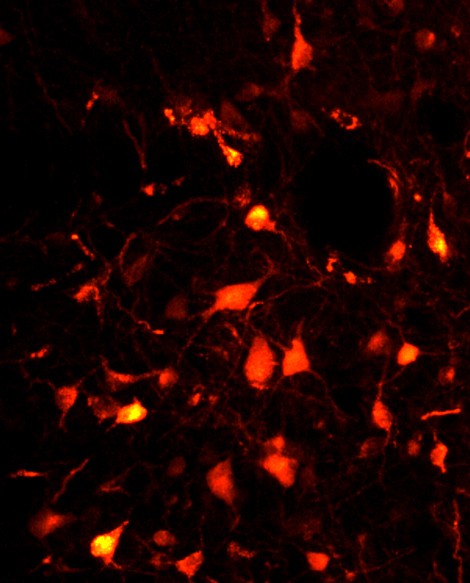

© Sara Valencia Garcia / Patrice Fort, CNRS The glutamate neurons of the sublaterodorsal nucleus emit a spontaneous red fluorescence indicating that the viral vectors used have been successfully added.

During REM sleep, the brain inhibits the motor system, which makes the sleeper completely immobile. CNRS researchers working in the Centre de Recherche en Neurosciences de Lyon (CNRS/Université Claude Bernard Lyon 1/INSERM/Université Jean Monnet) have identified a population of neurons that is responsible for this transient muscle paralysis. The animal model created will shed light on the origin of some paradoxical sleep disorders, and more particularly the condition that prevents this paralysis. It will also be most useful in the study of Parkinson's disease, since these pathologies are related. This work was published on December 12, 2016 on the website of the journal Brain . In spite of being in a deep sleep, the patients talk, move, kick and eventually fall out of bed. They are suffering from a parasomnia called REM Sleep Behavior Disorder1 (RBD).